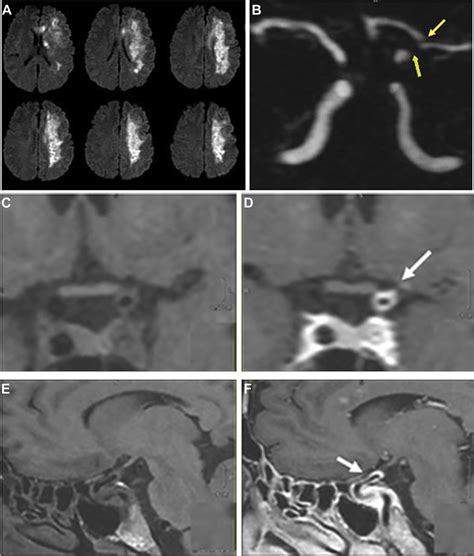

• Computed Tomography (CT) Scan: This is often the first imaging test performed in the emergency room setting for suspected stroke. A CT scan uses X-rays to create cross-sectional images of the brain. It’s excellent at quickly ruling out a hemorrhagic stroke , which is super important. While a standard non-contrast CT might not show the ischemic changes immediately (especially in the early hours), it can reveal signs of early ischemia like subtle loss of gray-white matter differentiation or a hyperdense artery (indicating a clot). Contrast-enhanced CT, like a CT angiography (CTA), is incredibly useful for visualizing the blood vessels and identifying the location of the clot or stenosis causing the ischemic event. CTA can show us where the blockage is and give us an idea of the vessel’s condition.

• Magnetic Resonance Imaging (MRI): MRI uses powerful magnets and radio waves to generate highly detailed images of the brain. It’s generally considered more sensitive than CT for detecting acute ischemic stroke, especially in the early stages. Different MRI sequences provide a wealth of information . For instance, diffusion-weighted imaging (DWI) is incredibly sensitive to the cytotoxic edema that occurs within minutes of an ischemic event, allowing for very early detection of infarction. Perfusion-weighted imaging (PWI) can assess blood flow through the brain tissue, helping to identify areas of compromised perfusion that might be salvageable. MRI angiography (MRA) is another technique used to visualize the blood vessels, similar to CTA but without the ionizing radiation. While MRI offers superior detail, it takes longer than a CT scan and may not be readily available in all emergency settings, and patients with certain implants might not be able to undergo the scan.